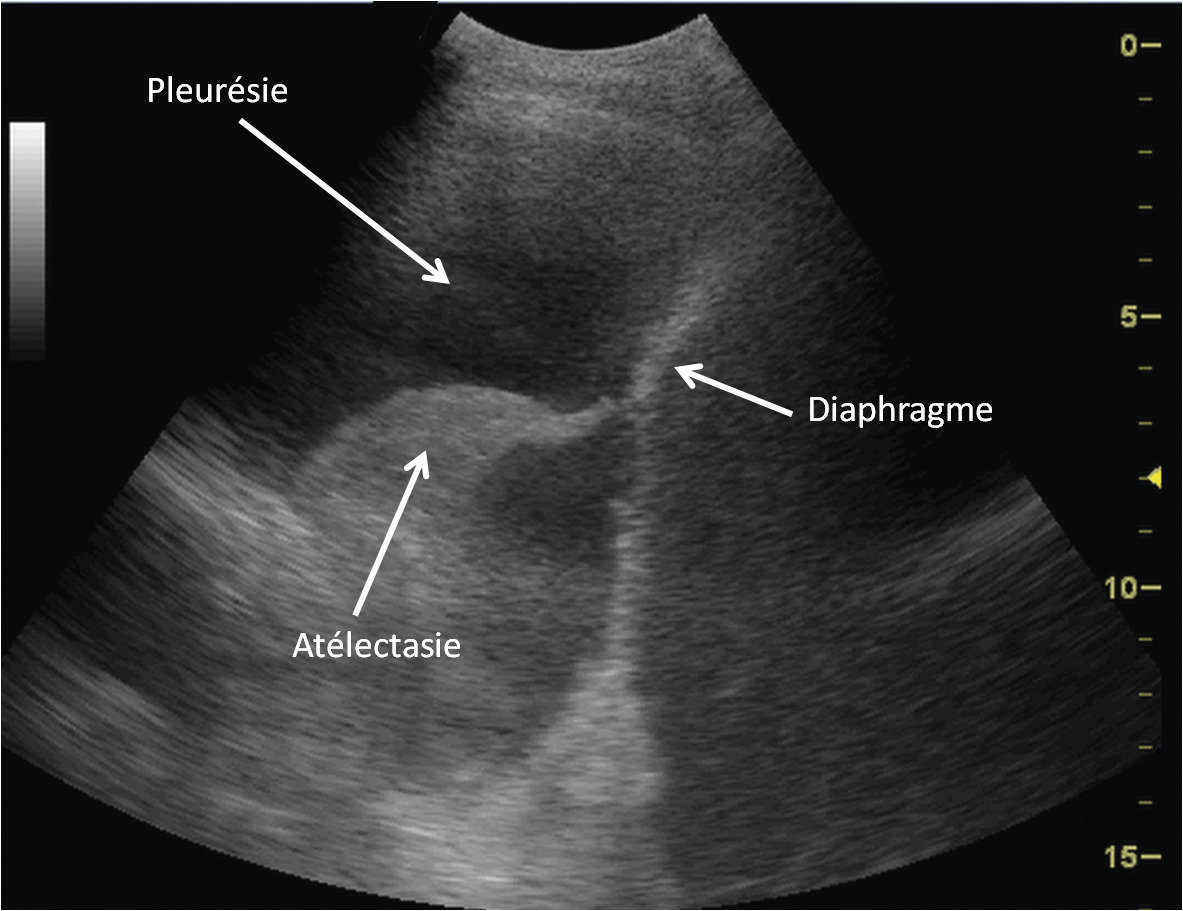

L’échographie est mieux adaptée que la radiographie thoracique pour le diagnostic des pleurésies, en particulier parapneumoniques. Elle permet un suivi évolutif en évaluant de manière plus précise l’abondance de la pleurésie (fig. 1 ).